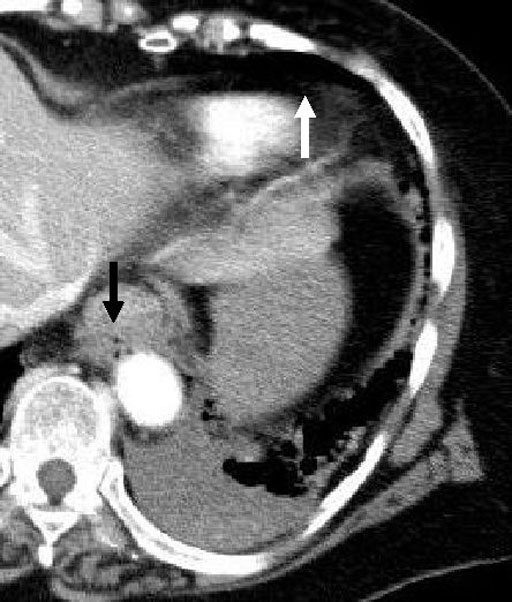

造影CT(図3-c)

食道壁の肥厚および壁内のガス泡(黒矢印),遊離ガス(白矢印),背側が高濃度呈する胸水を認める.

胸部単純写真(図1)では左肺の透過性が低下しており,左胸水の存在が疑われる.遊離ガスは指摘できない. 胸部CT(図2,3)では下部食道壁の肥厚が認められる.背側壁内にガス泡が認められ,心嚢腹側には遊離ガス像認める.左胸水認める.背側が高濃度となっており,食道破裂が胸腔に穿破し,内容が貯留しているものと思われる. 手術所見:食道左側後壁の粘膜に4㎝ の縦走する裂創を認め,胸腔内には多量の食物残渣を認めた.